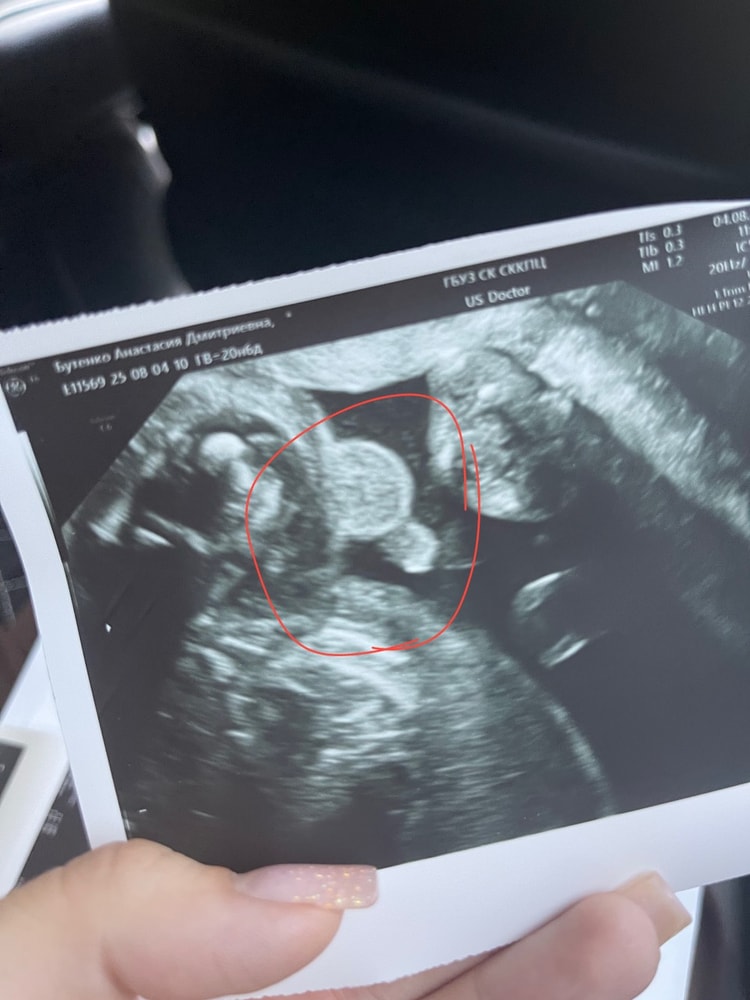

Всё о нашей беременностиСегодня был второй скрининг,20 недель и 6 дней😄

малыш во всю пинается с 15 недель🥰,иногда даже не дает уснуть,тк пик активности у него именно ночью😂 его вес 350 гр на сегодняшний день🍈